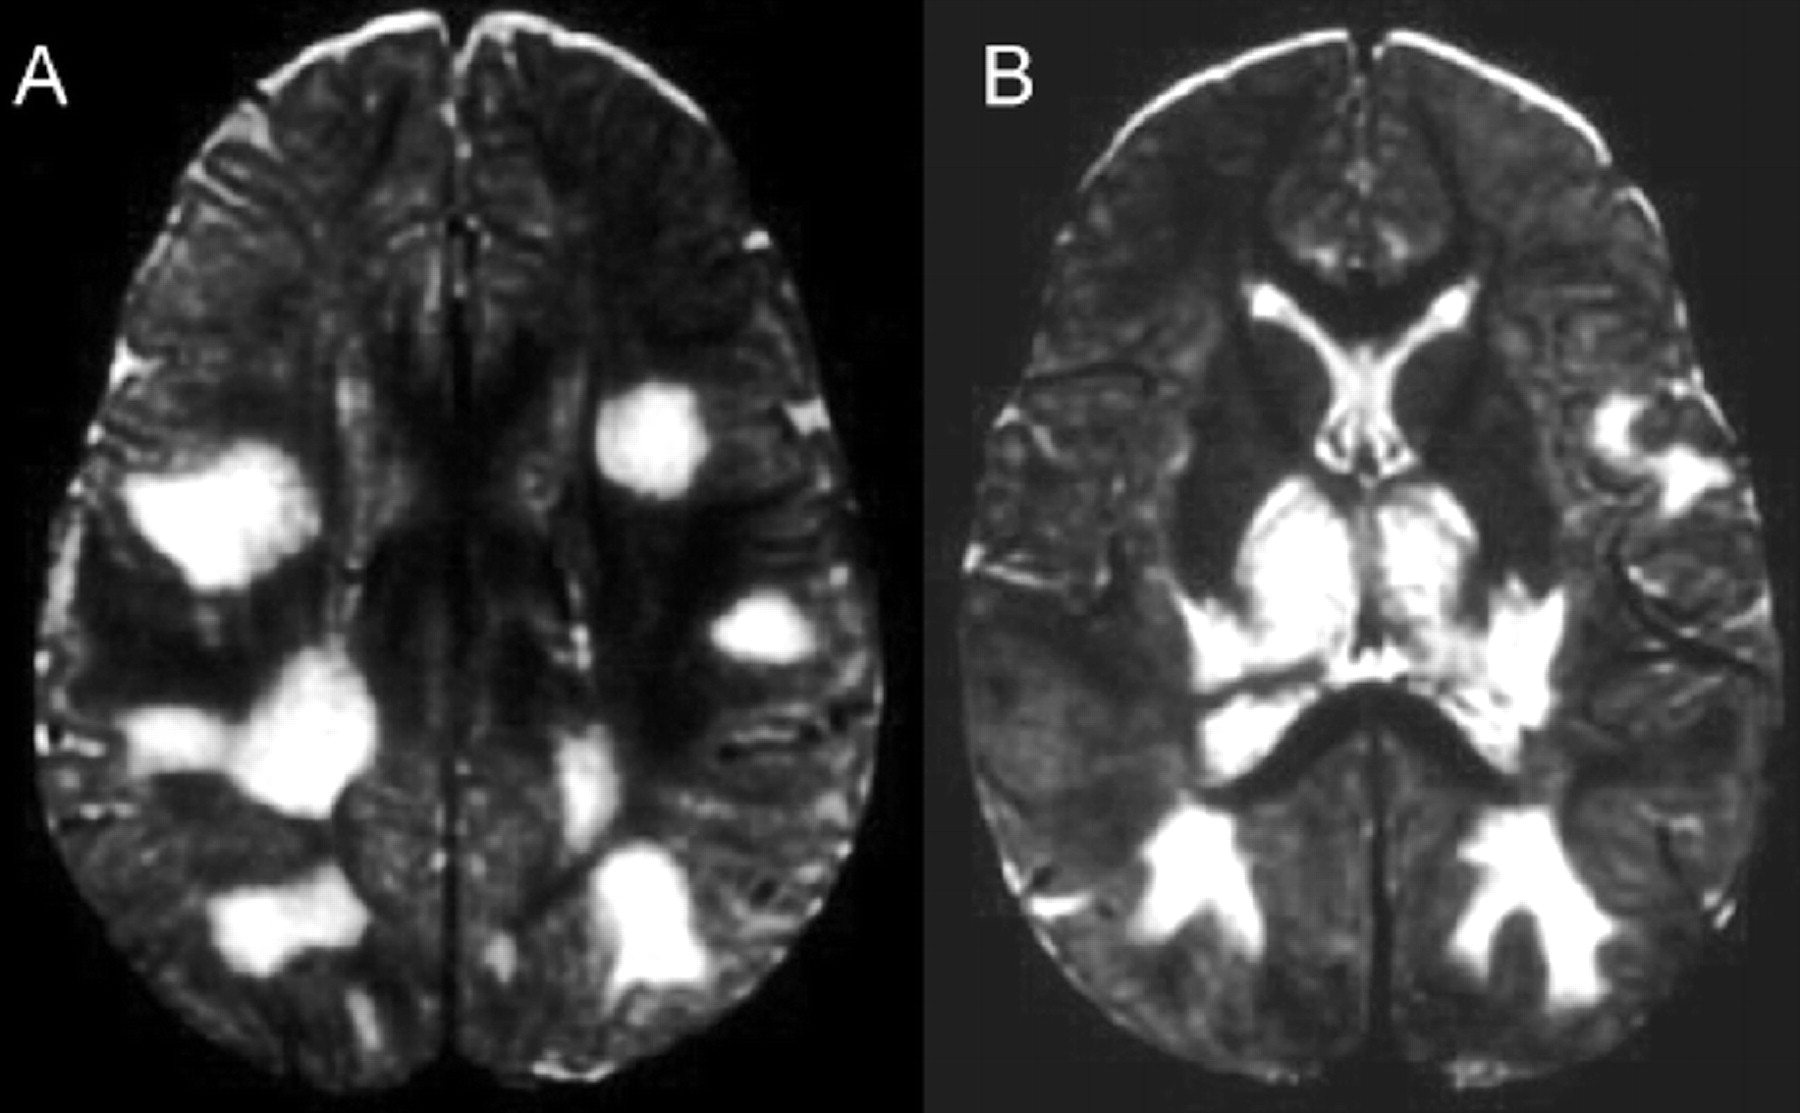

提出了四种模式的大脑参与描述ADEM的磁共振成像结果21:1)ADEM小病变(少于5毫米;图1);2)ADEM大支流,块状病变,簇状或频繁广泛perilesional水肿和质量效应(图2);3)ADEM附加对称bithalamic参与(图3);和4)急性出血性脑脊髓炎(咳咳),当一些出血的证据可以确定大脱髓鞘病变(图4)。核磁共振成像模式似乎并不与任何特定的结果或残疾,作为大型儿童群体中观察到,21因为大多数病变往往解决后续成像研究。21日,32然而,这种分类可能是有用的在考虑的鉴别诊断ADEM和可能有助于识别那些孩子来说,初始ADEM-phenotype真的是第一个女士的表现。

神经影像学在建立ADEM的诊断是非常重要的。在t2加权MRI异常最常见的确定和fluid-attenuated反转恢复序列(天赋)是不完整的,不加边的区域信号强度增加。病变ADEM通常大,多个,和不对称。他们通常涉及到皮层下和中央白质和皮质灰白色结两脑半球,小脑、脑干和脊髓。30.花托和基底神经节的灰质经常参与,通常在一个对称的模式。21日,31日室周的白质也经常参与,被描述为30 - 60%的病例。20日,22日,30岁胼胝体病变局限于不太常见。然而,大型邻近白质脱髓鞘病变可能延伸到胼胝体和交叉侧半球。